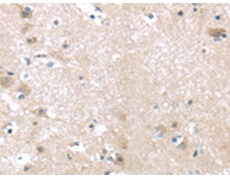

IHC positive control:

Human brain and Human liver cancer

IHC Recommend dilution:

10-50